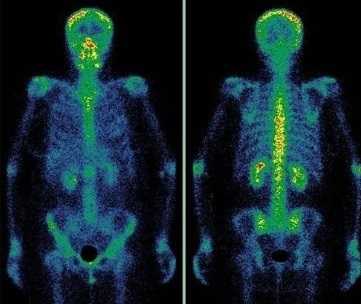

Сцинтиграфия костей скелета (остеосцинтиграфия) – исследование метаболизма (обмена веществ) костной ткани с помощью радиофармацевтических препаратов (РФП), которые накапливаются в костях скелета. Радиофармпрепарат вводится внутривенно и затем излучение от накопившегося препарата улавливается детекторами регистрирующего прибора (гамма-камеры).

Диагностику заболеваний костей скелета проводят с меченными фосфатными комплексами, которые прочно связываются с кристаллами гидроксиапатита и незрелым коллагеном. В качестве метки используется 99мТс, который имеет короткий период полураспада – всего 6 ч. Гамма-кванты покидают организм и регистрируются детекторами прибора, в результате после компьютерной обработки получается изображение.

Метастазы различных опухолей в кости

Многие опухоли метастазируют в кости. В первую очередь подозрение на метастатическое поражение скелета возникает при раке молочной и предстательной желез, раке легкого и почек. Особую настороженность следует проявлять при увеличении уровня онкомаркеров ПСА (простатспецифический антиген), СА 15-3 и некоторых других. После консервативного лечения или хирургического удаления опухоли рекомендуется динамическое наблюдение за состоянием костной ткани. Сцинтиграфию следует проводить первые 2 раза с промежутком 6-8 месяцев, затем, при нормальном результате исследования - через 1–2 года.